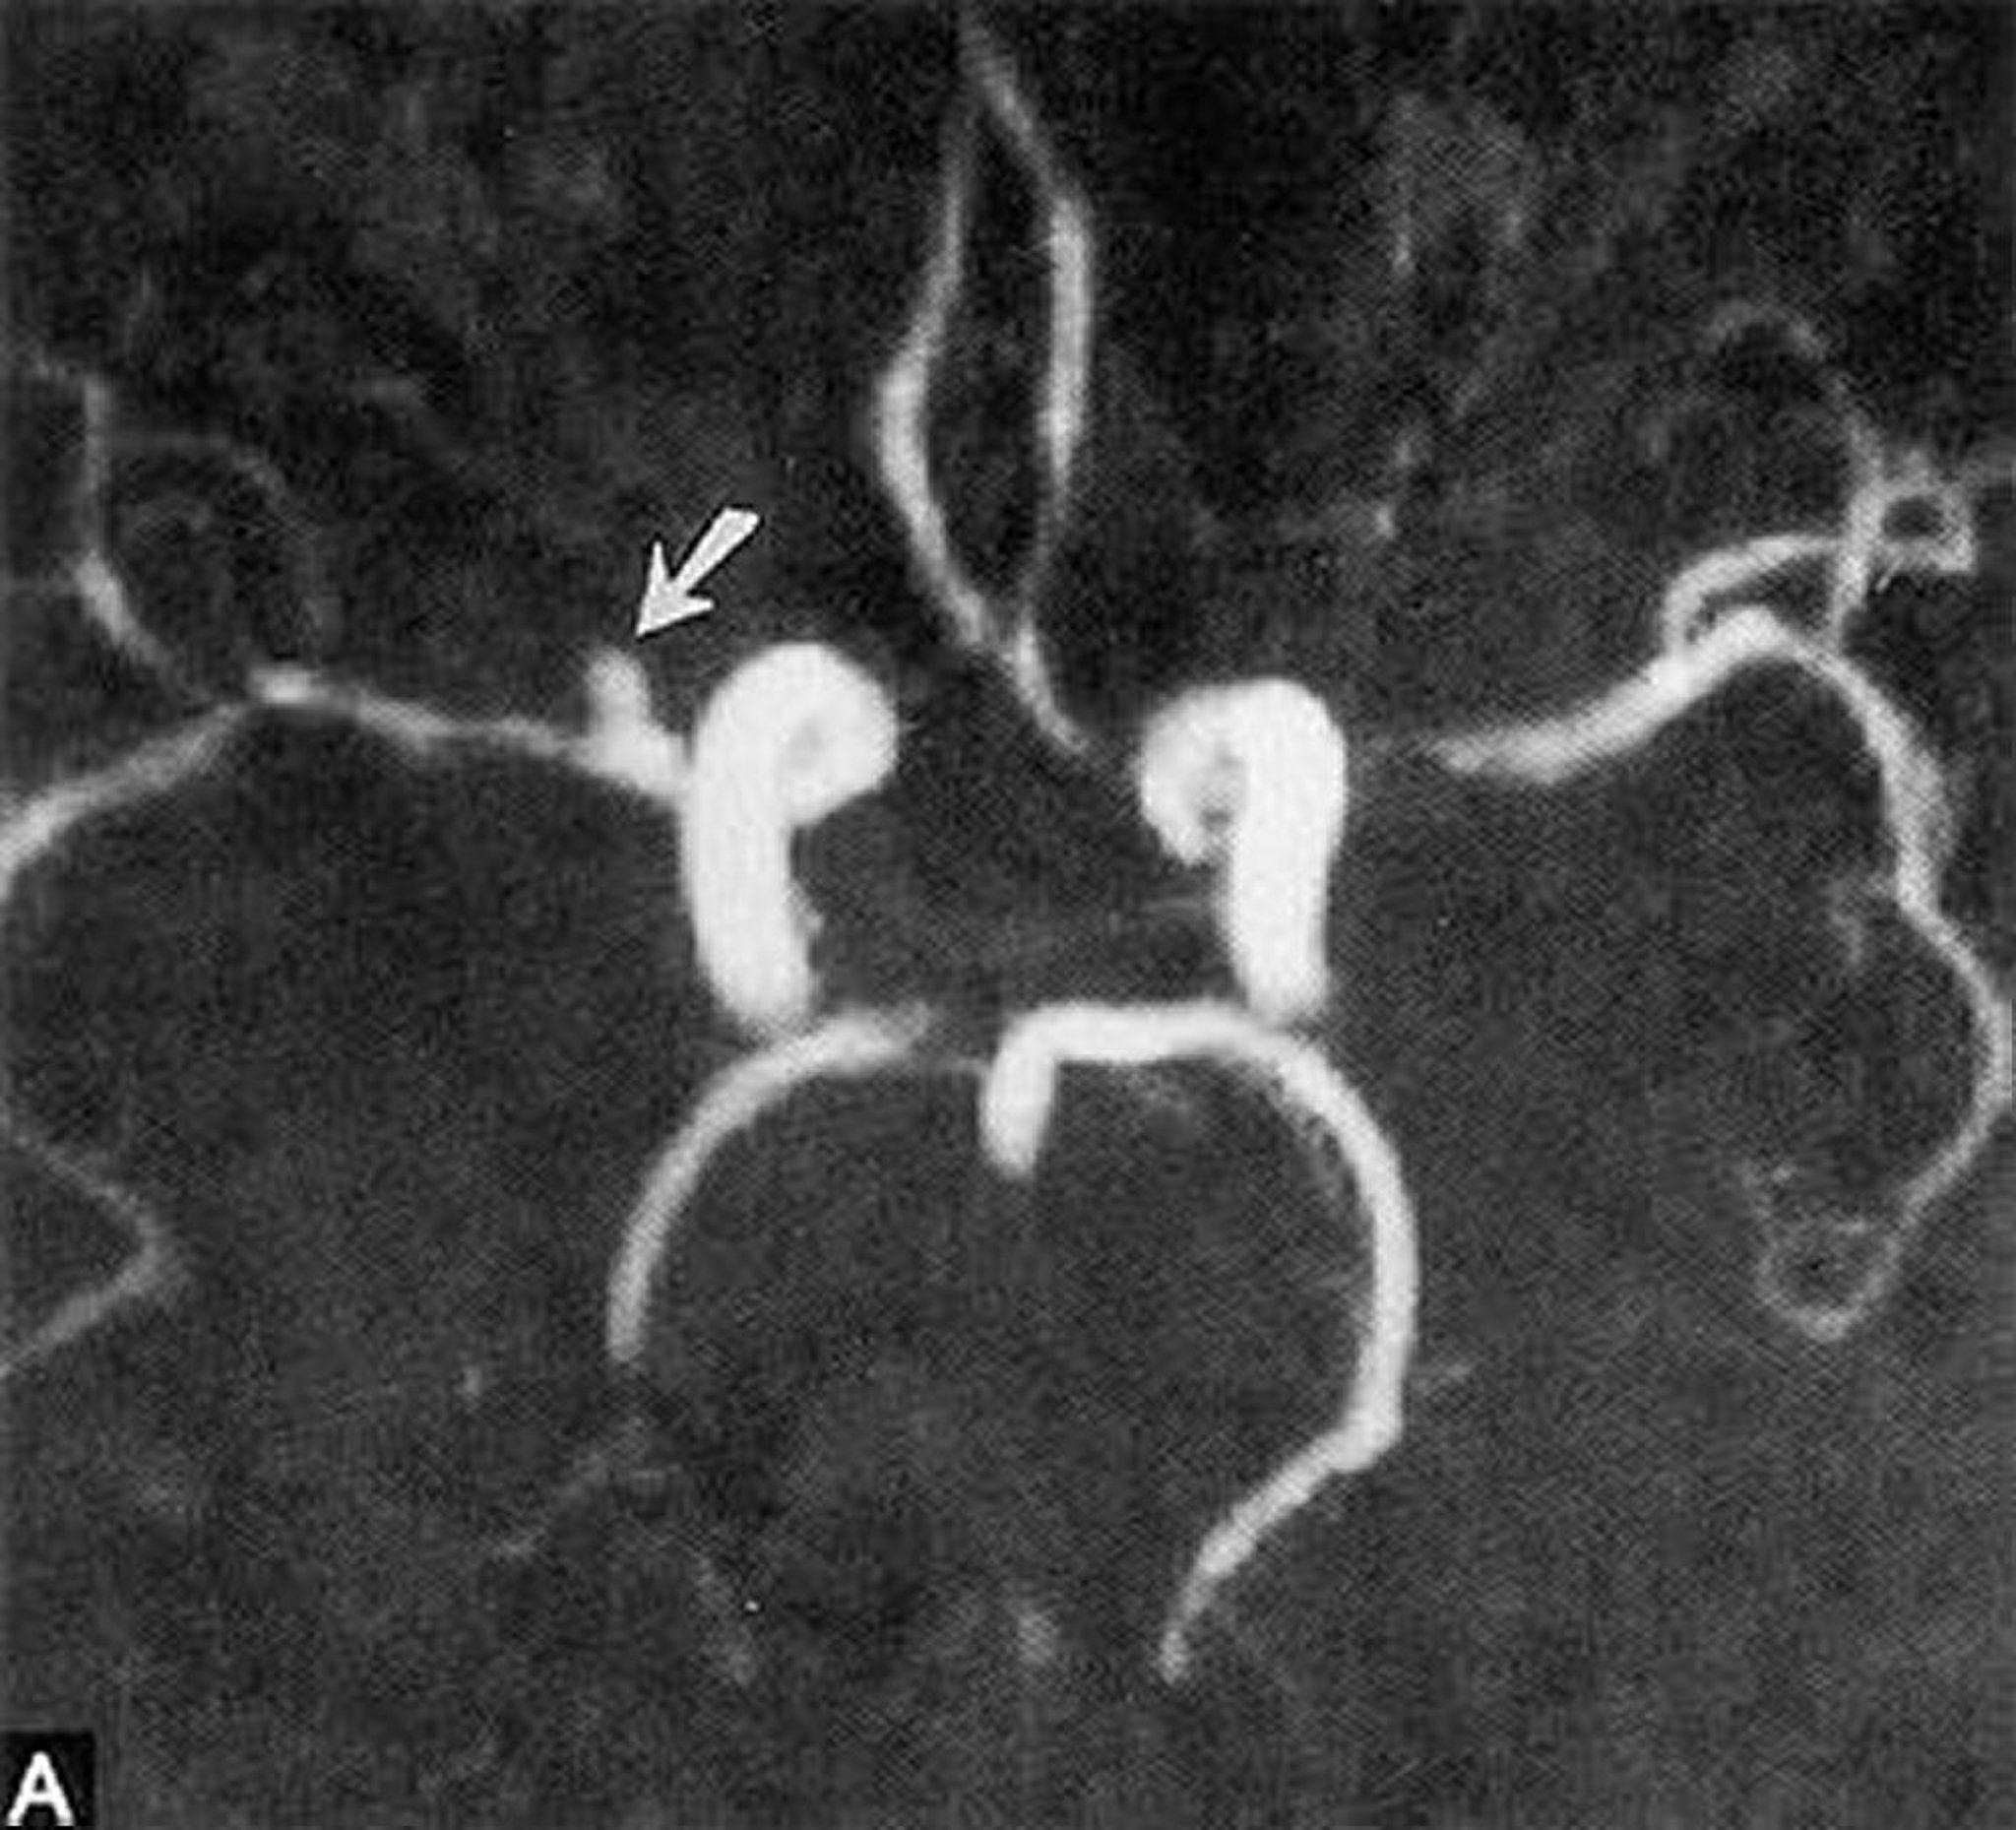

Aneurisma sacular

Essa angiografia por ressonância magnética mostra um pequeno aneurisma sacular da artéria cerebral média direita horizontal (seta).

By permission of the publisher. From Ritter A, Hayman L, Charletta D. In Atlas of Cerebrovascular Disease. Edited by PB Gorelick and MA Sloan. Philadelphia, Current Medicine, 1996.